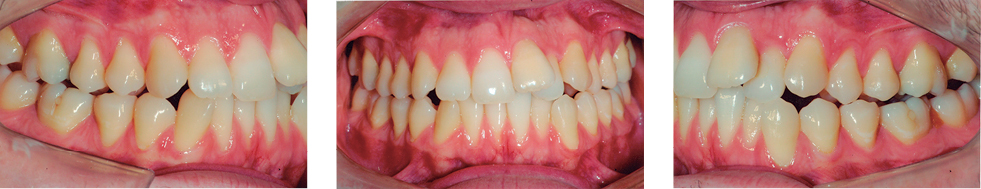

Figura 2: Fotografias extra e intraorais iniciais.